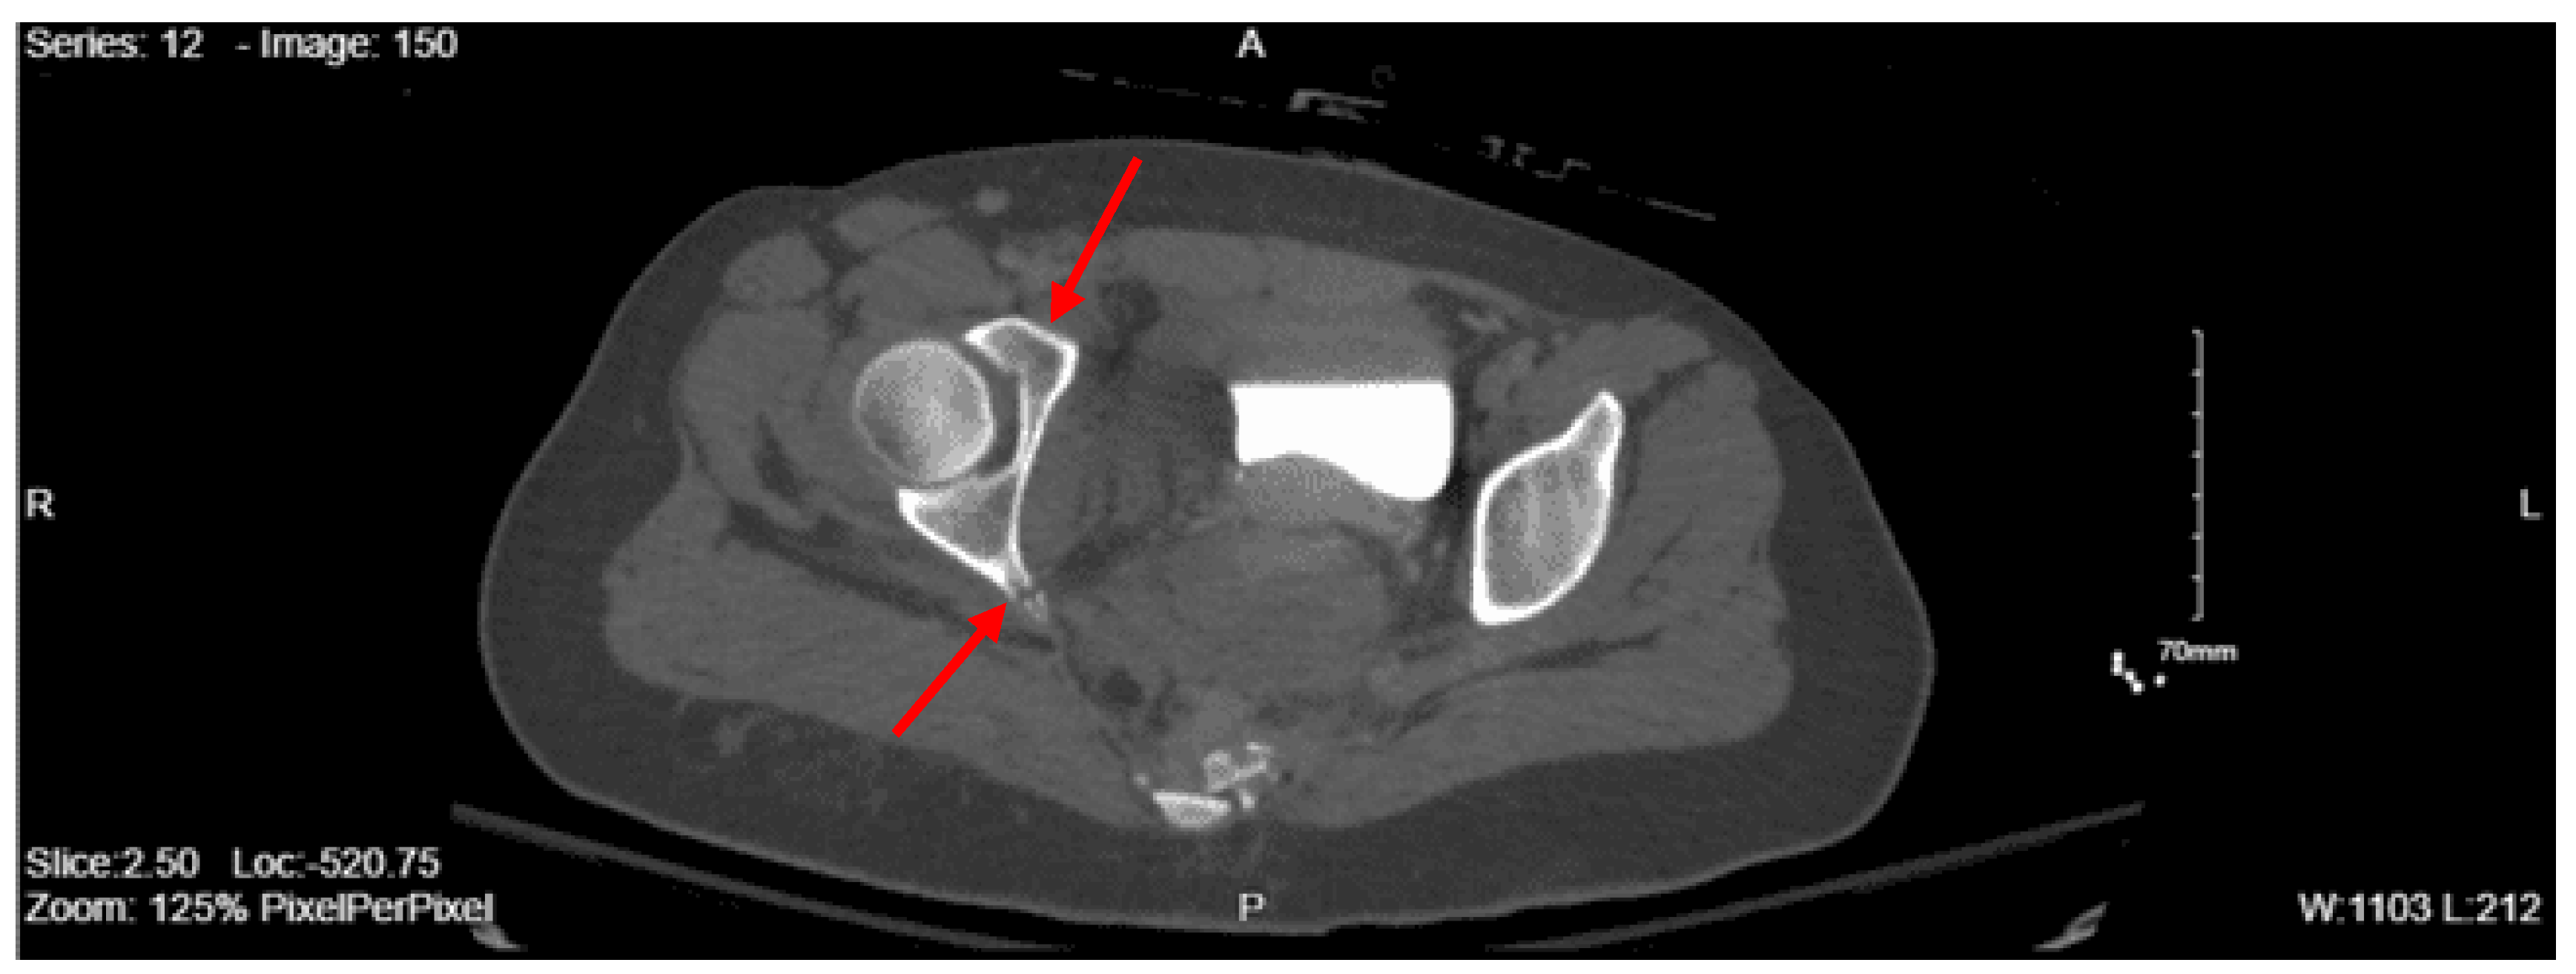

Imaging as shown in Figure 1, Figure 2 and Figure 3:

CT lumbar spine w/o contrast: An acute comminuted fracture is seen involving the superior portion of the left sacral wing. The SI joints are intact. Intact lumbar spine.

CT abdomen/pelvis with contrast: Acute fractures are seen involving the right superior pubic ramus and left inferior pubic ramus. An acute comminuted avulsed fracture of the left sacral wing in the superior and midportion is demonstrated. No definitive acute traumatic visceral abnormalities were found throughout the abdomen and pelvis.

DX: Denis zone II left sacral alar fx involving S1 foramina. AOSpine B3: NX, M3